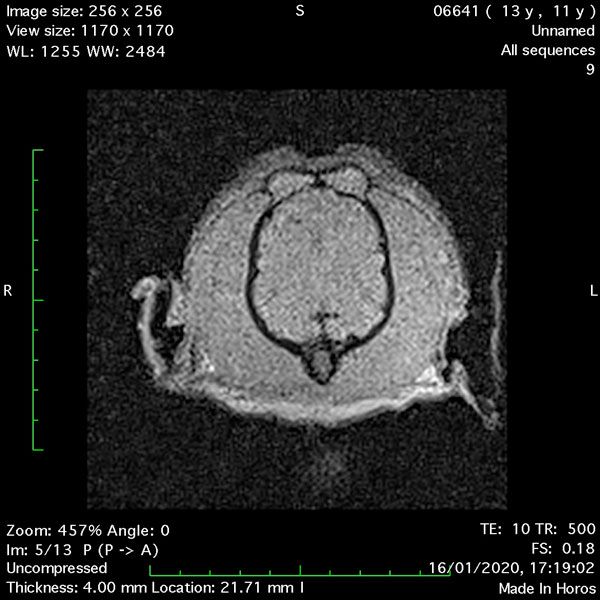

- Transverse T1 – Spin Echo T1 (post-contrast) (Figure 4);

MRI images were viewed in DICOM format (Digital Imaging and Communications in Medicine) (Figures 1-7) and assessed in-house under the guidance of a board-certified radiologist. The series were evaluated for changes in intensity in the T1- and T2-weighted sequences (T1w and T2w, respectively). There was a 4mm x 7mm x 7mm intra-axial, wedge-shaped hyperintense reasonably-well demarcated region in the right cerebrum visible in the T2w images (Figures 2-3). This was consistent with a focal infarct. No contrast enhancement, anatomical abnormality nor space occupying lesion was noted in the T1w sequences (Figure 1, Figure 4). There was no observed pathology on assessment of the FLAIR images (Figure 5).

Figures 1-7: Images obtained with MRI depicted in sequential order and assessed under the guidance of a board-certified radiologist in-house.